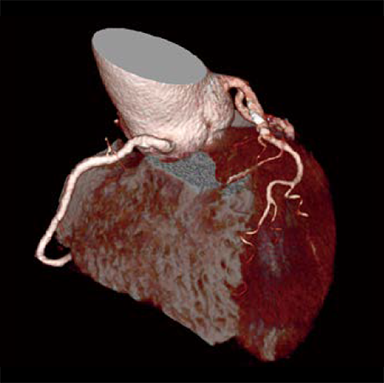

Cardio StillShot: OFF

Cardio StillShot: ON